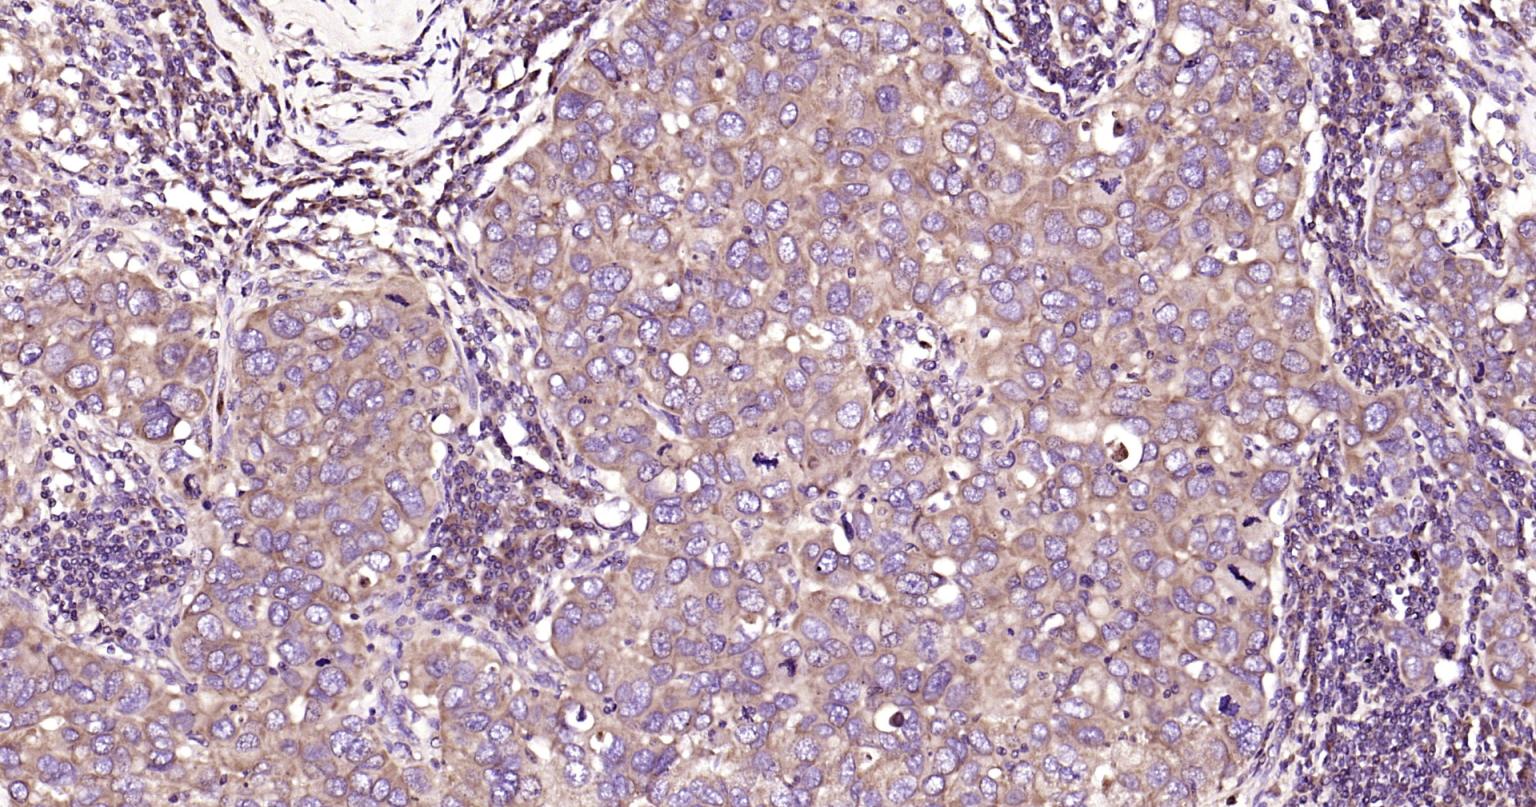

| IHC-P | Human, Mouse, Rat | Rabbit | 1:400-800 |